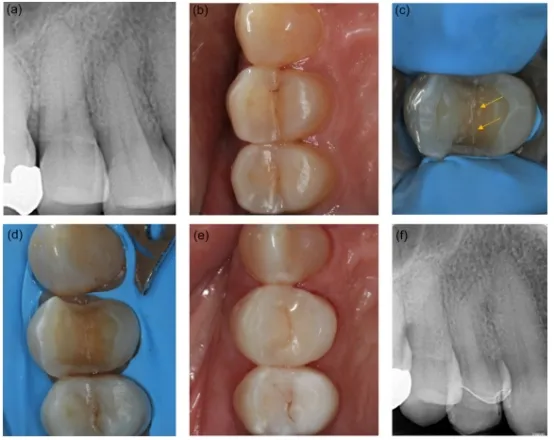

对于活髓牙隐裂的治疗决策目前尚无共识。有专家认为需要先进行根管治疗后行全冠修复,也有学者采取磨除裂纹后直接树脂充填、嵌体修复或者进行全冠修复。Ricucci等发现,隐裂纹是细菌侵入牙髓的路径,当裂纹扩展至牙髓时,细菌的代谢产物和毒性物质发生微渗漏,刺激牙髓出现症状,可能导致牙髓炎症甚至牙髓坏死。因此彻底去除隐裂纹,消除细菌侵入的途径,安抚治疗缓解牙髓症状,有利于验证可复性牙髓炎的诊断、评估剩余牙体结构、修复价值及长期预后。直接修复是一种治疗龋齿或者修复牙体缺损的简单而有效的方法,可在单次就诊中完成。Opdam等人对39颗有或没有牙尖覆盖的直接修复的牙隐裂进行了随访。在7年的随访中,只有3颗没有牙尖覆盖的牙需要进行根管治疗。Banerji认为树脂充填是短期治疗手段,早期进行高嵌体或冠修复治疗的远期预后相对较好 ,不覆盖尖牙的直接修复牙的牙髓成活率为73.8%~76.7%。与全冠修复相比,活髓牙隐裂在直接修复后期出现的拔牙风险高8倍,需要根管治疗的可能性高3倍。全冠既可进行有效的冠方封闭,防止细菌侵入牙髓组织通道。也可有效地环抱患牙,产生紧箍效应可以使咬合力直接传递至牙根,分散合力,因此牙尖覆盖的修复被推荐用于牙隐裂。

图4:在完整裂纹 14 的间接复合高嵌体修复

(a)术前根尖周 X 光片(b)咬合视图(c) 裂纹线显示(箭头)(d) 高嵌体制备 (e) 术后咬合视图,结合间接复合高嵌体 (f) 随访 6 个月根尖周 X 光片,这颗牙齿仍然有生命力且无症状